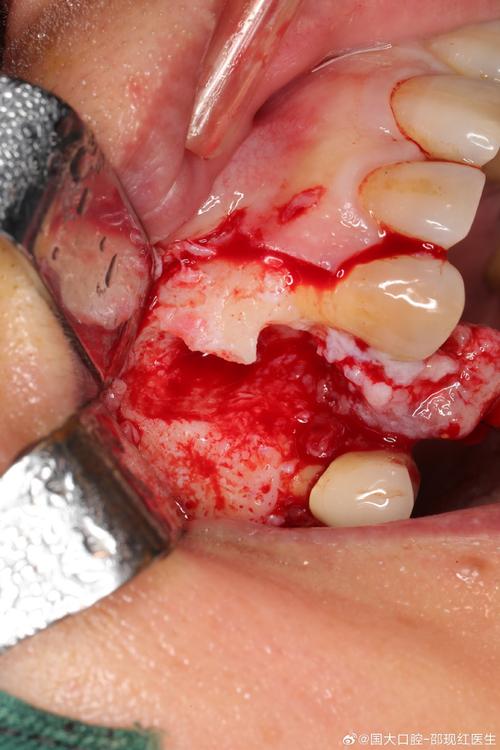

(图片来源网络,侵删)- 牙龈愈合与塑形: 种植手术后,牙龈组织会自然地向上生长,包裹住种植体颈部,形成袖口状的牙龈轮廓,这是种植体成功的关键一步,这个过程需要几周到几个月。

- 软组织手术:

- 牙龈切除术/成形术: 切除增生的牙龈组织,恢复健康的牙龈袖口形态。

- 翻瓣术+骨增量: 如果骨吸收较严重,需要翻开牙龈,清创,并进行骨移植。